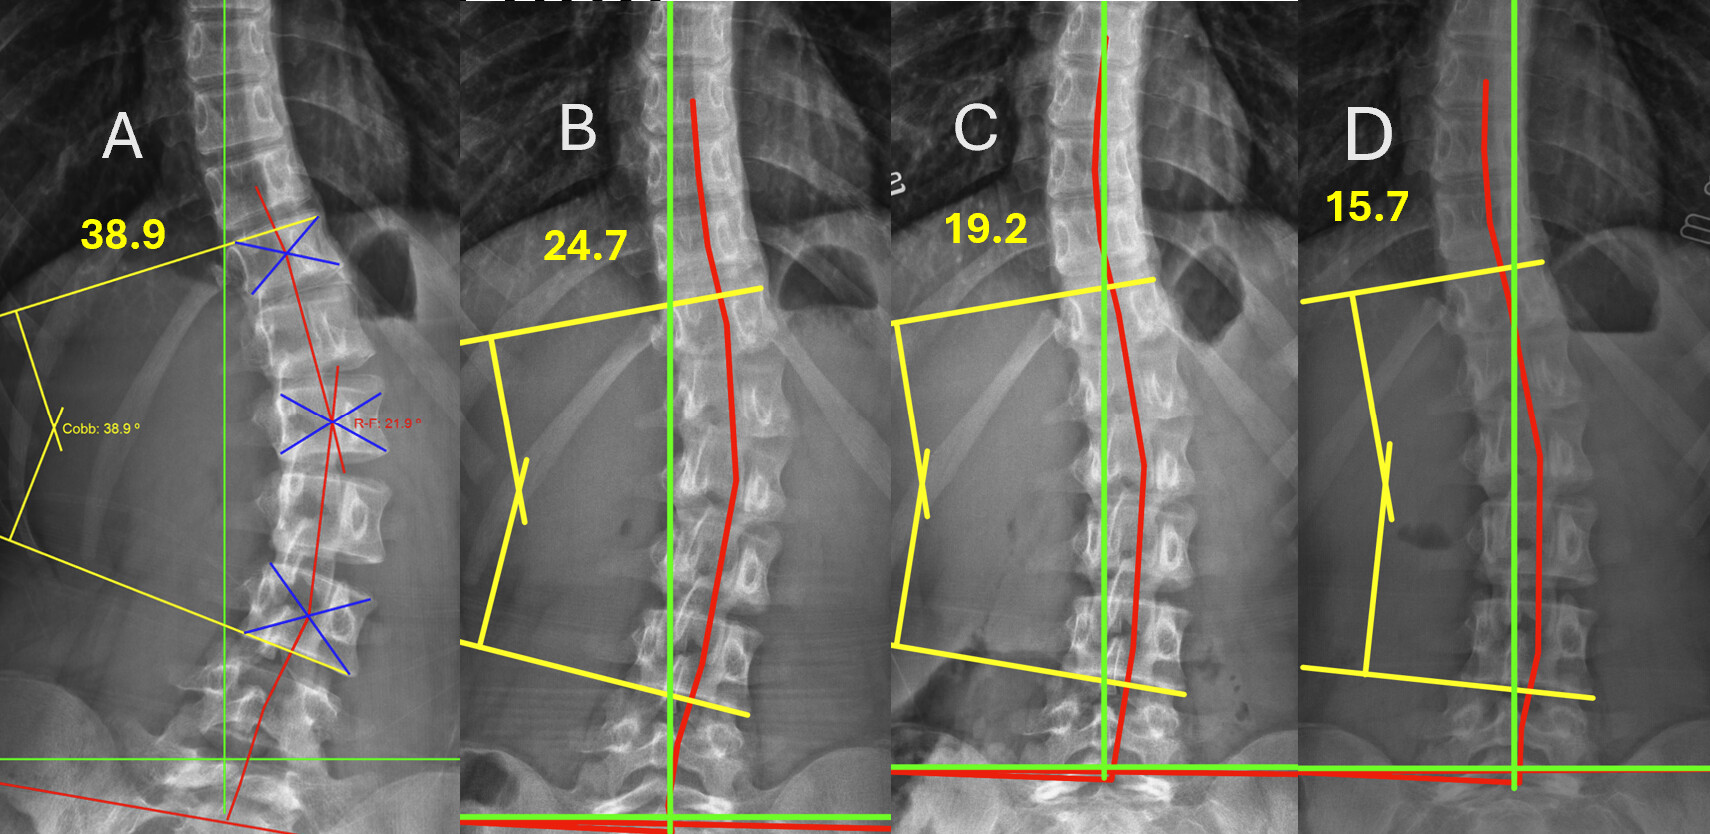

Results of a 2 week intensive with a 1 year follow up.